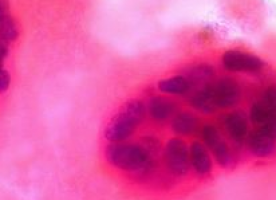

Isocitrate dehydrogenases (IDHs) are enzymes involved in chemical reactions that generate energy within cells. Mutations in IDH have been identified in several cancer types, including gliomas — cancers that originate in the glial cells in the brain.

Timothy Chan and co-workers show that mutation of IDH1 promotes epigenetic changes to the DNA in glial cells, and these epigenetic alterations are the same as those found in a certain subclass of glioma. Their findings provide a possible pathway linking IDH mutations to the formation of tumours.

In a second study, Craig Thompson and colleagues find other epigenetic changes resulting from expression of mutant IDH enzymes. Mutant IDH produces the metabolite 2-hydroxyglutarate (2HG), which impairs demethylation of histones and prevents cells from differentiating normally, and thus could contribute to tumour development.